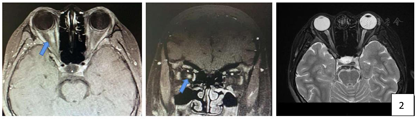

结核药物治疗期间因异烟肼及乙胺丁醇导致视力受损的情况是在临床治疗过程中较为多见的副作用,当患者处于抗痨治疗期间,出现视力损害很容易让临床医生联想到结核药物的影响。但是为什么会在第二次规范抗痨过程中出现视力损害?为什么双侧视力损害不是同时出现?且双侧视力受损程度不一致?在当地医院停用异烟肼、乙胺丁醇后视神经的损害迟迟得不到恢复,是停药时间不够?还是已经出现永久性视神经损害?是否都可以用"药物性视神经损害"解释?或者还有其他原因?带着这样的疑问进行眼科、神经内科、药学部MDT讨论。眼科建议:复查眼底照片、vEP、ERG、FFA、OCT及裂隙灯检查。为除外合并眼结核以及评价视神经是否损害,同时预约眼眶MRI。药学部建议:患者使用的四联抗结核药物中,乙胺丁醇和异烟肼均可能引起视神经病变,其中乙胺丁醇的可能性最大,且其严重程度呈时间和剂量依赖性,早期发现和及时停药可于数周到数月消失,极少数发生永久性视觉功能丧失。同时考虑患者出现结核全身多处转移,抗结核治疗仍需坚持,建议利福平+吡嗪酰胺联合治疗。神经内科建议:完善腰穿、脑脊液及血液送抗水通道蛋白-4抗体检测;同时完善颈胸髓及眼眶MRI(图2、图3),眼眶MRI示双侧视神经鞘膜积液,右侧视神经球后段强化明显,考虑炎性改变。颈胸髓质长段异常信号影。

初步诊断:1.淋巴结结核,培阳,复治,依据:患者有明确淋巴结结核病史,初始治疗疗程不足,本次入院前再次出现颈部淋巴结肿大,淋巴结穿刺培养提示结核分枝杆菌2+,故诊断明确。2.结核性腹膜炎,依据:患者有结核感染基础,曾有不规律治疗史,本次起病存在腹痛、腹水形成,经过抗痨治疗后腹水吸收,故诊断。3.双眼视力障碍原因待查:(1)药物性损害?依据:该患者确诊结核并使用一线方案治疗,抗痨药物中异烟肼、乙胺丁醇可能导致视神经损害,故考虑诊断。但停用结核药物后该患者视力无恢复,仍呈进行性下降,此表现不支持药物性损害特点。(2)眼结核?依据:患者有结核感染基础,前期不规律治疗可能导致结核潜伏,其次结核存在全身多系统感染特征,是否因眼部结核感染导致视力受损需警惕,但眼部MRI成像不符合眼结核特征,支持依据不足。(3)视神经脊髓谱系病?依据:患者视力损害呈进行性加重,起病过程双眼视力损害程度不同,眼部及颈胸髓MRI可见视神经及脊髓异常信号影。脑脊液抗水通道蛋白-4抗体7.15 U/ml(阳性);血清抗水通道蛋白-4抗体80 U/ml(阳性),故诊断明确。